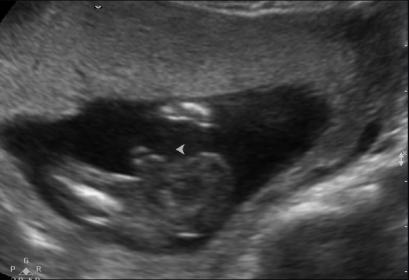

HI everyone just wondering what is everyone thoughts about our new bubba, we have a 2 year old daughter. Thanks

Nub...is...tilted/pointed...upwards!!!

BOY!

Thanks for such a quick reply ! I did, mostly boy guesses, but a tech said girl so now im confused, and wanted to try this site aswell. I think the tech said girl because of the second photo because of the fork in the nub and also because the end of the spine isnt visble. I think that it could go either way because the nub isnt 30 degrees but then its not pointing down either. My DD's nub was pointing really far down so it was obvious, but this one is driving me mad lol 5 more days till we find out!!! WOO HOO!

cracker, this is what I was thinking? Also baby is quite curled and I'm seeing the nub quite in line with it if i straighten baby out. But! The nub does look quite fat so thinking boy and it doesn't seem to be completely attached to the body so leaning boy on that one also. I would have to say 65/35 boy on your nub but will be waiting anxiously on your result, hope you hear blue: What is the gestation??